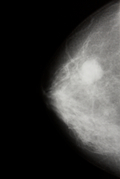

Фиброаденома молочной железы  —  доброкачественная опухоль молочной железы, происходящая из клеток самой железы, возникающая на фоне гормонального нарушения.  Является разновидностью узловой мастопатии.

В молочной железе прощупывается безболезненное опухолевидное образование размером от 0,2 см до 7см, гладкое, плотное,  смещающееся при ощупывании.

В диагностике фиброаденом используется маммография (рентгеновское исследование молочной железы), УЗИ, пункция (биопсия) и осмотр маммолога.

Прогноз благоприятный.  После операции по удалению опухоли могут возникать новые фиброаденомы.